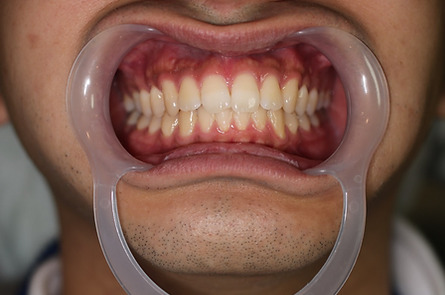

6入れ歯にしないブリッジ治療【ケース3】

このケースの患者さんは上の歯の歯槽膿漏が心配で来院されました。上の歯は11本残っており、下の写真の緑色に囲われた歯を1本抜歯して、計10本の歯を使って端から端まで繋げる治療を行いました。H22.5月に治療が始まり、H23.1月に完成しました。

以下の写真はR4.9月に撮影した写真です。

2022年現在72歳の女性の方です。

治療が終了してから13年経過していますが、今も大丈夫です。